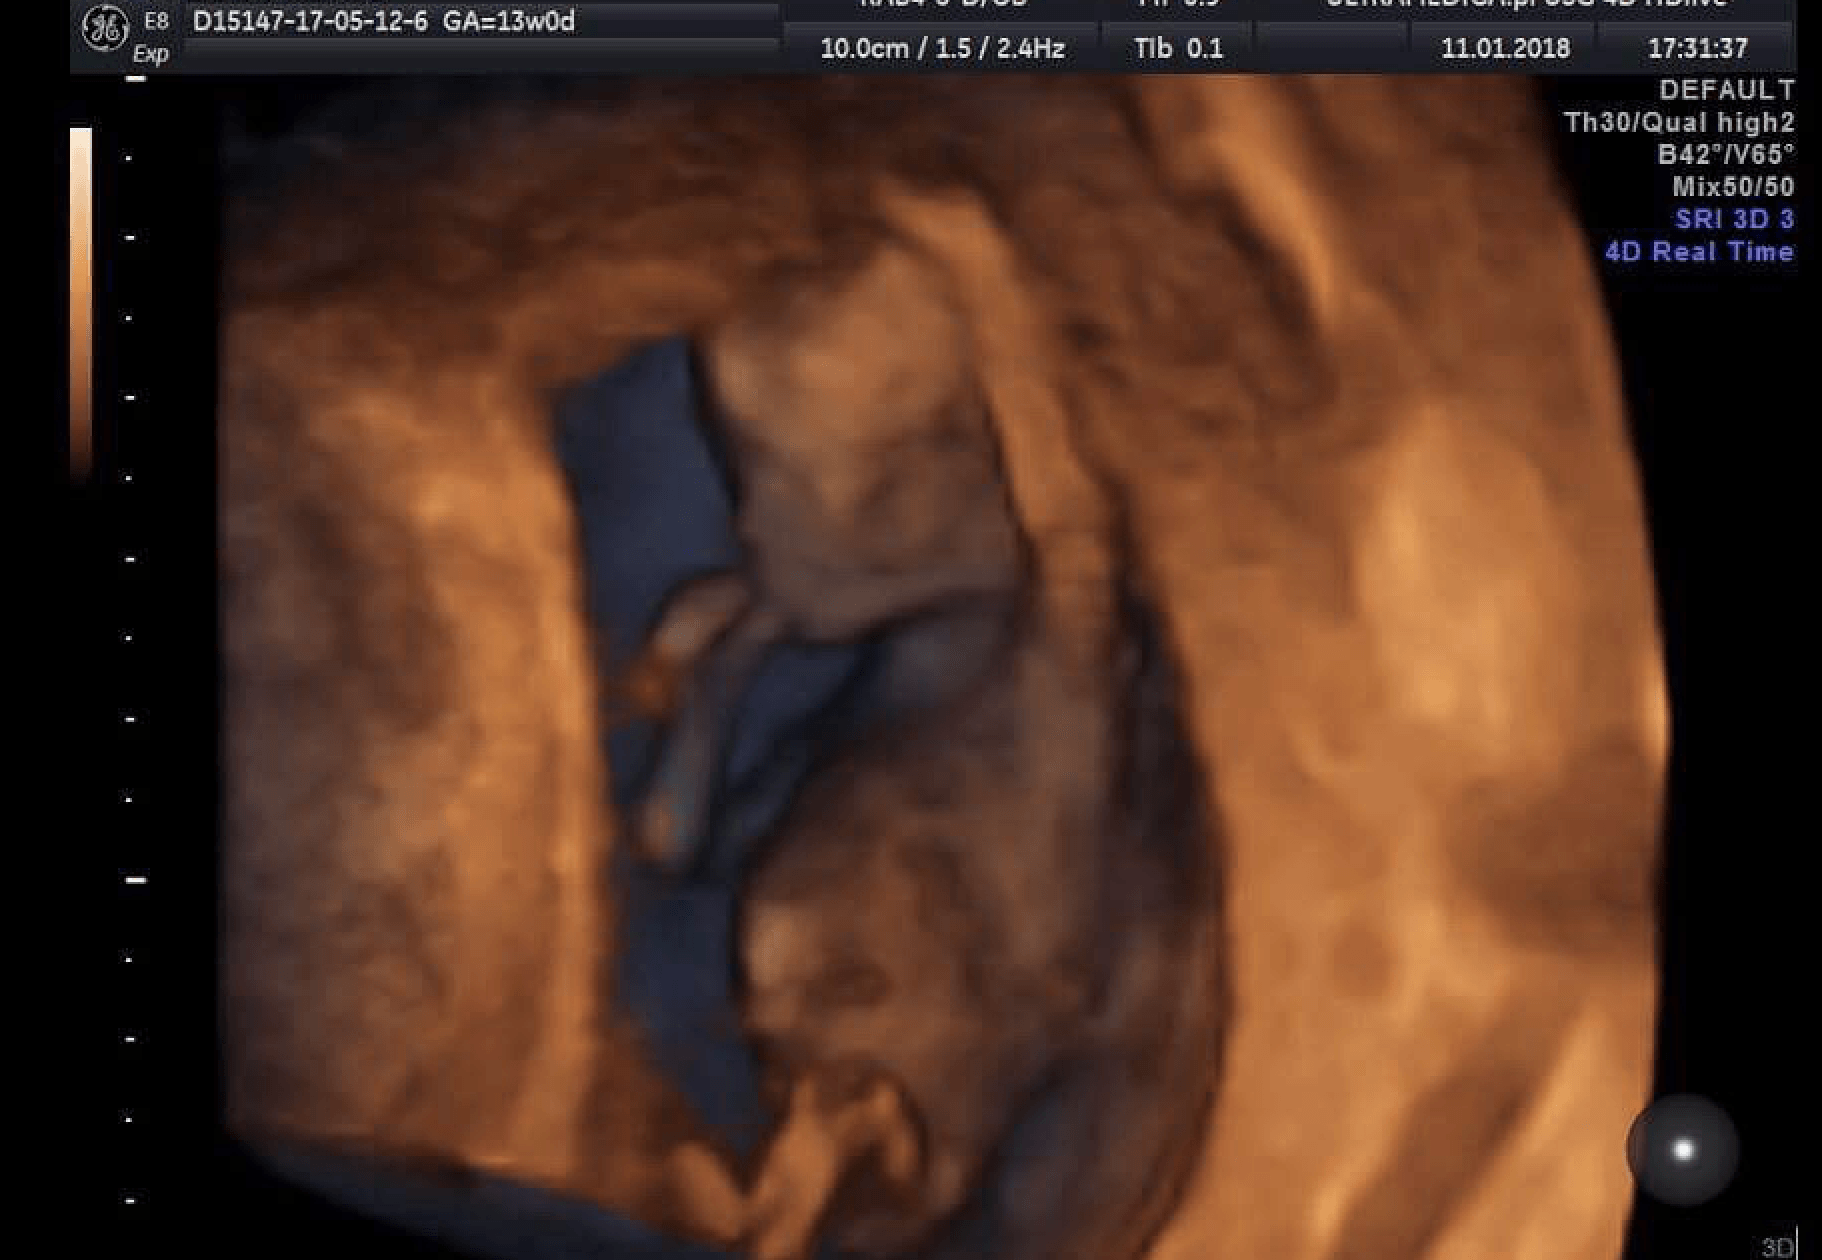

Proszę bardzo :) To zdjęcie mojego małego "kosmitki" z dnia 11.01.2018:

@olaaa7 To zdjęcie było zrobione w 13t0d, czyli 2 tygodnie temu mniej więcej. Maluch miał wtedy 7 cm. Nie miałam filmiku niestety, ale teraz gin obiecał mi, że przy każdym usg będzie mi dodawał obraz 4d (bez dodatkowej opłaty). Samo usg 4d, moim zdaniem, bardzo fajna sprawa. Można zobaczyć maluszka w zupełnie innym wizerunku :) no i podejrzewam, że im większa dzidzia, tym lepsza jakość takie zdjęcia :) Ja jestem zachwycona!